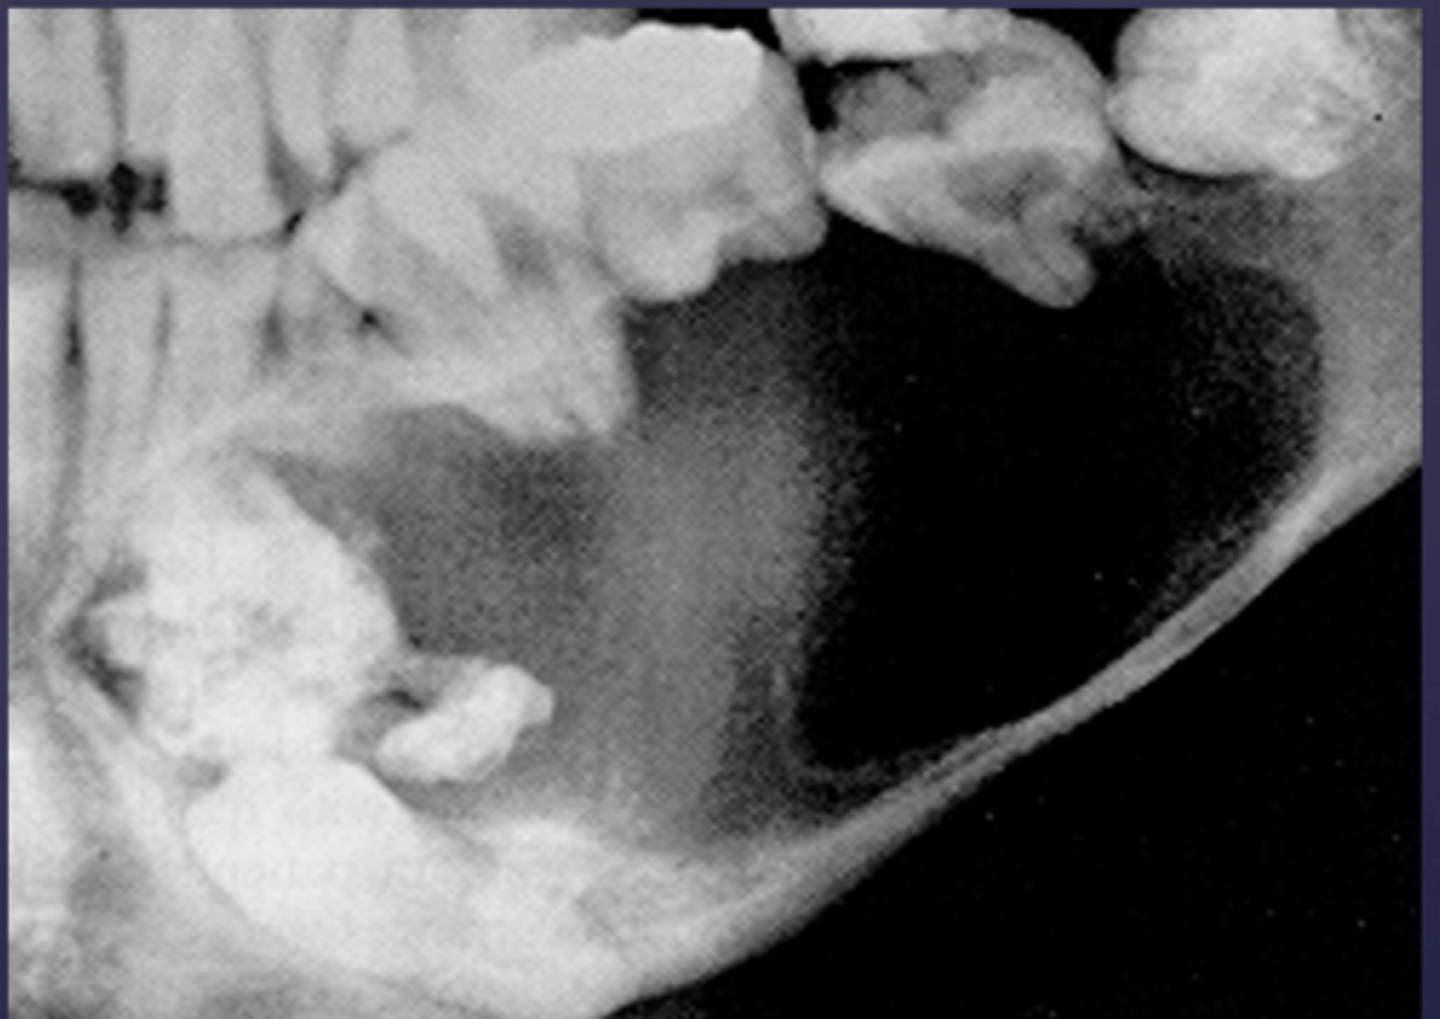

how would you describe the lesion?

A. well-defined, corticated, pericoronal radiolucency associated with tooth number 7

B. well-defined, non coritcated periapical lesion associated with tooth number 6

C. ill-defined, corticated periapical lesion associated with tooth number 6

D. ill-defined, corticated periapical lesion associated with tooth number 5

(root resorption also seen)

What category would you put this lesion into?

Benign odontogenic tumor/cyst

What would be a differential diagnosis for this lesion?

- AOT

- Calcifying Epithelial Odontogenic Tumor (Pindborg tumor)

- Calcifying Epithelial Odontogenic Cyst( Gorlins cyst)